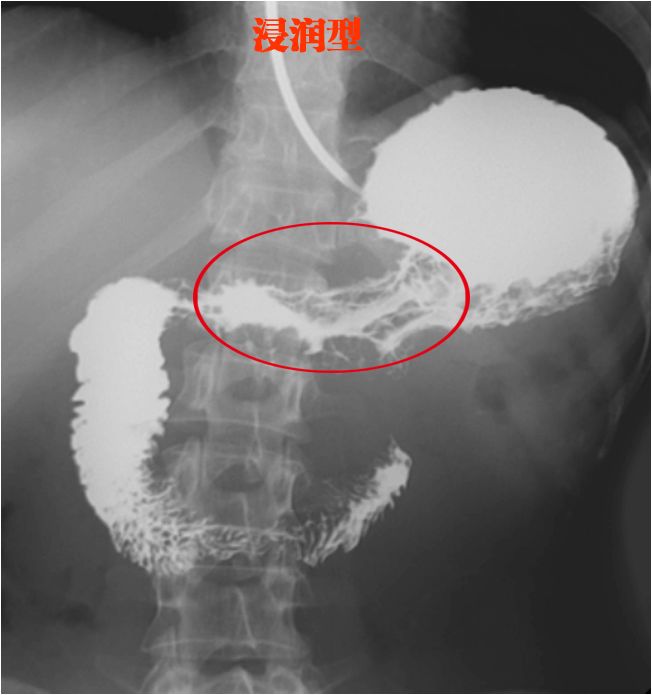

浸润型

肿瘤沿着胃壁生长

把胃壁搞得失去弹性

变得很窄,所以只能看到一点钡剂

看图